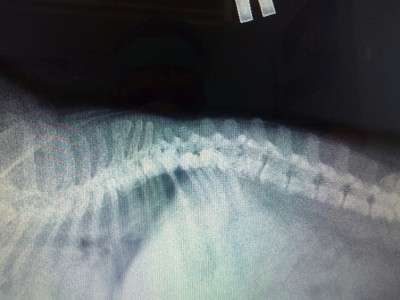

Может кто то что то подскажет по снимку

Натэлла, На правом боку. Передние лапки вверх держали, задние назад

Inna, Да, Сотников пишет: " позвонки не разрушены. Они такие у всех собак этой породы.....". Ягников по снимкам ничего не может сказать, почему-не знаю. Лечение СС правильное. И то, что приступы с позвоночником не связаны. На форумы ещё не писала. Но напишу обязательно. Давыдов пока не отписался.

На мой взгляд, там есть дегенеративные изменения, но полностью разрушенными я их не назову. Конечно, в таких случаях желательно МРТ позвоночника, для уточнения.